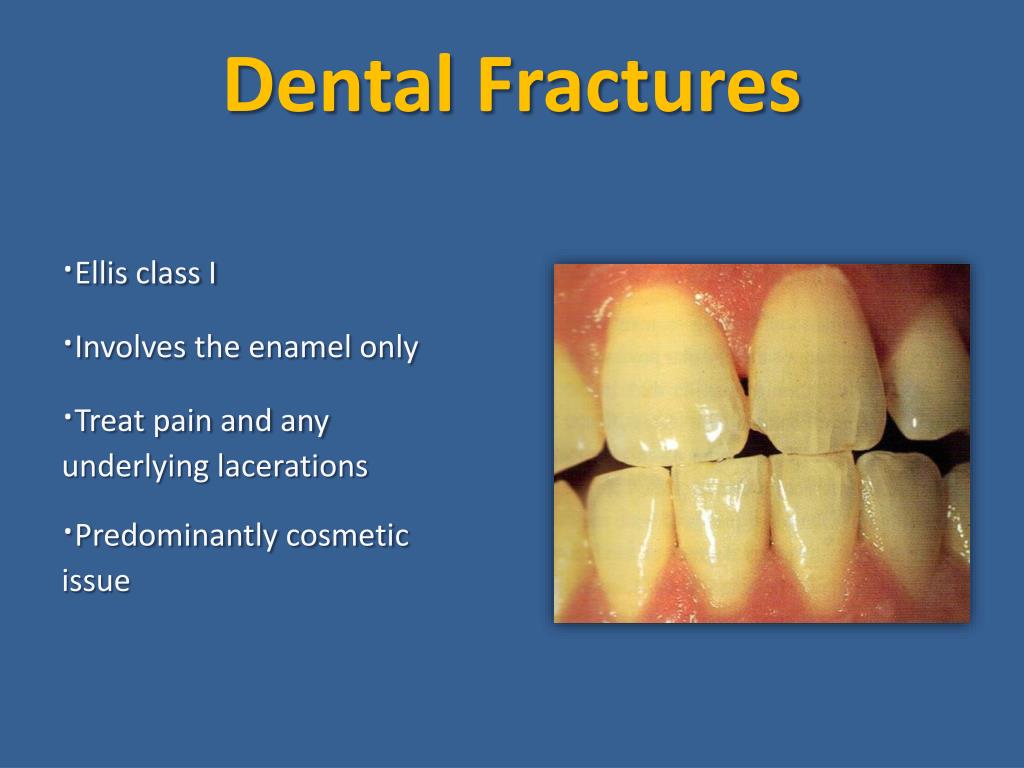

PPT - Facial Trauma PowerPoint Presentation, Free Download - ID:2392727

www.slideserve.com

www.slideserve.com

dental ellis fractures ppt powerpoint facial trauma class enamel involves presentation underlying only